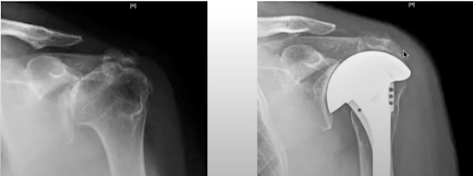

A 71 year old active man presented with pain, stiffness and weakness of the right shoulder after prior rotator cuff surgery. He had active and passive elevation of his right arm to 90 degrees.

His radiographs are shown below

and Hamada 4B